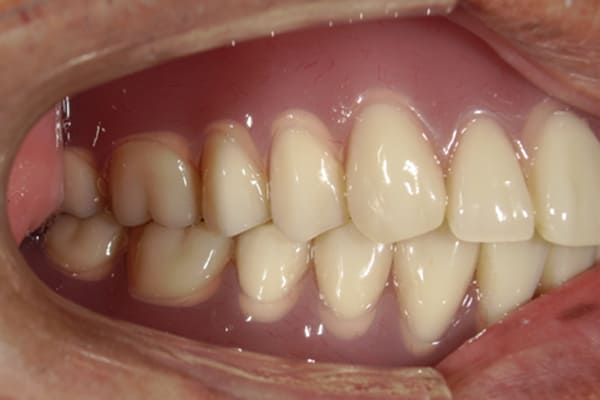

治療後は、入れ歯により受け口も治し正常のお口元に。

治療前は上の入れ歯の歯のラインが湾曲し、下の歯が前に出ているのが分かります。

治療後は、歯のラインが真っすぐとなり、下の歯も正常のかみ合わせになっています。

金属を用いた総入れ歯の欠点に、歯茎がやせ、外れやすくなった際、裏打ちをする修理が困難であることが挙げられます。

しかし、右のお写真のように、後ろのみプラスチックを用いることで、金属を用いた場合と同じ装着感は保ったまま、プラスチック部を裏打ちすることで、入れ歯が外れにくいよう修理が可能となります。

受け口も改善され、自然なお口元に